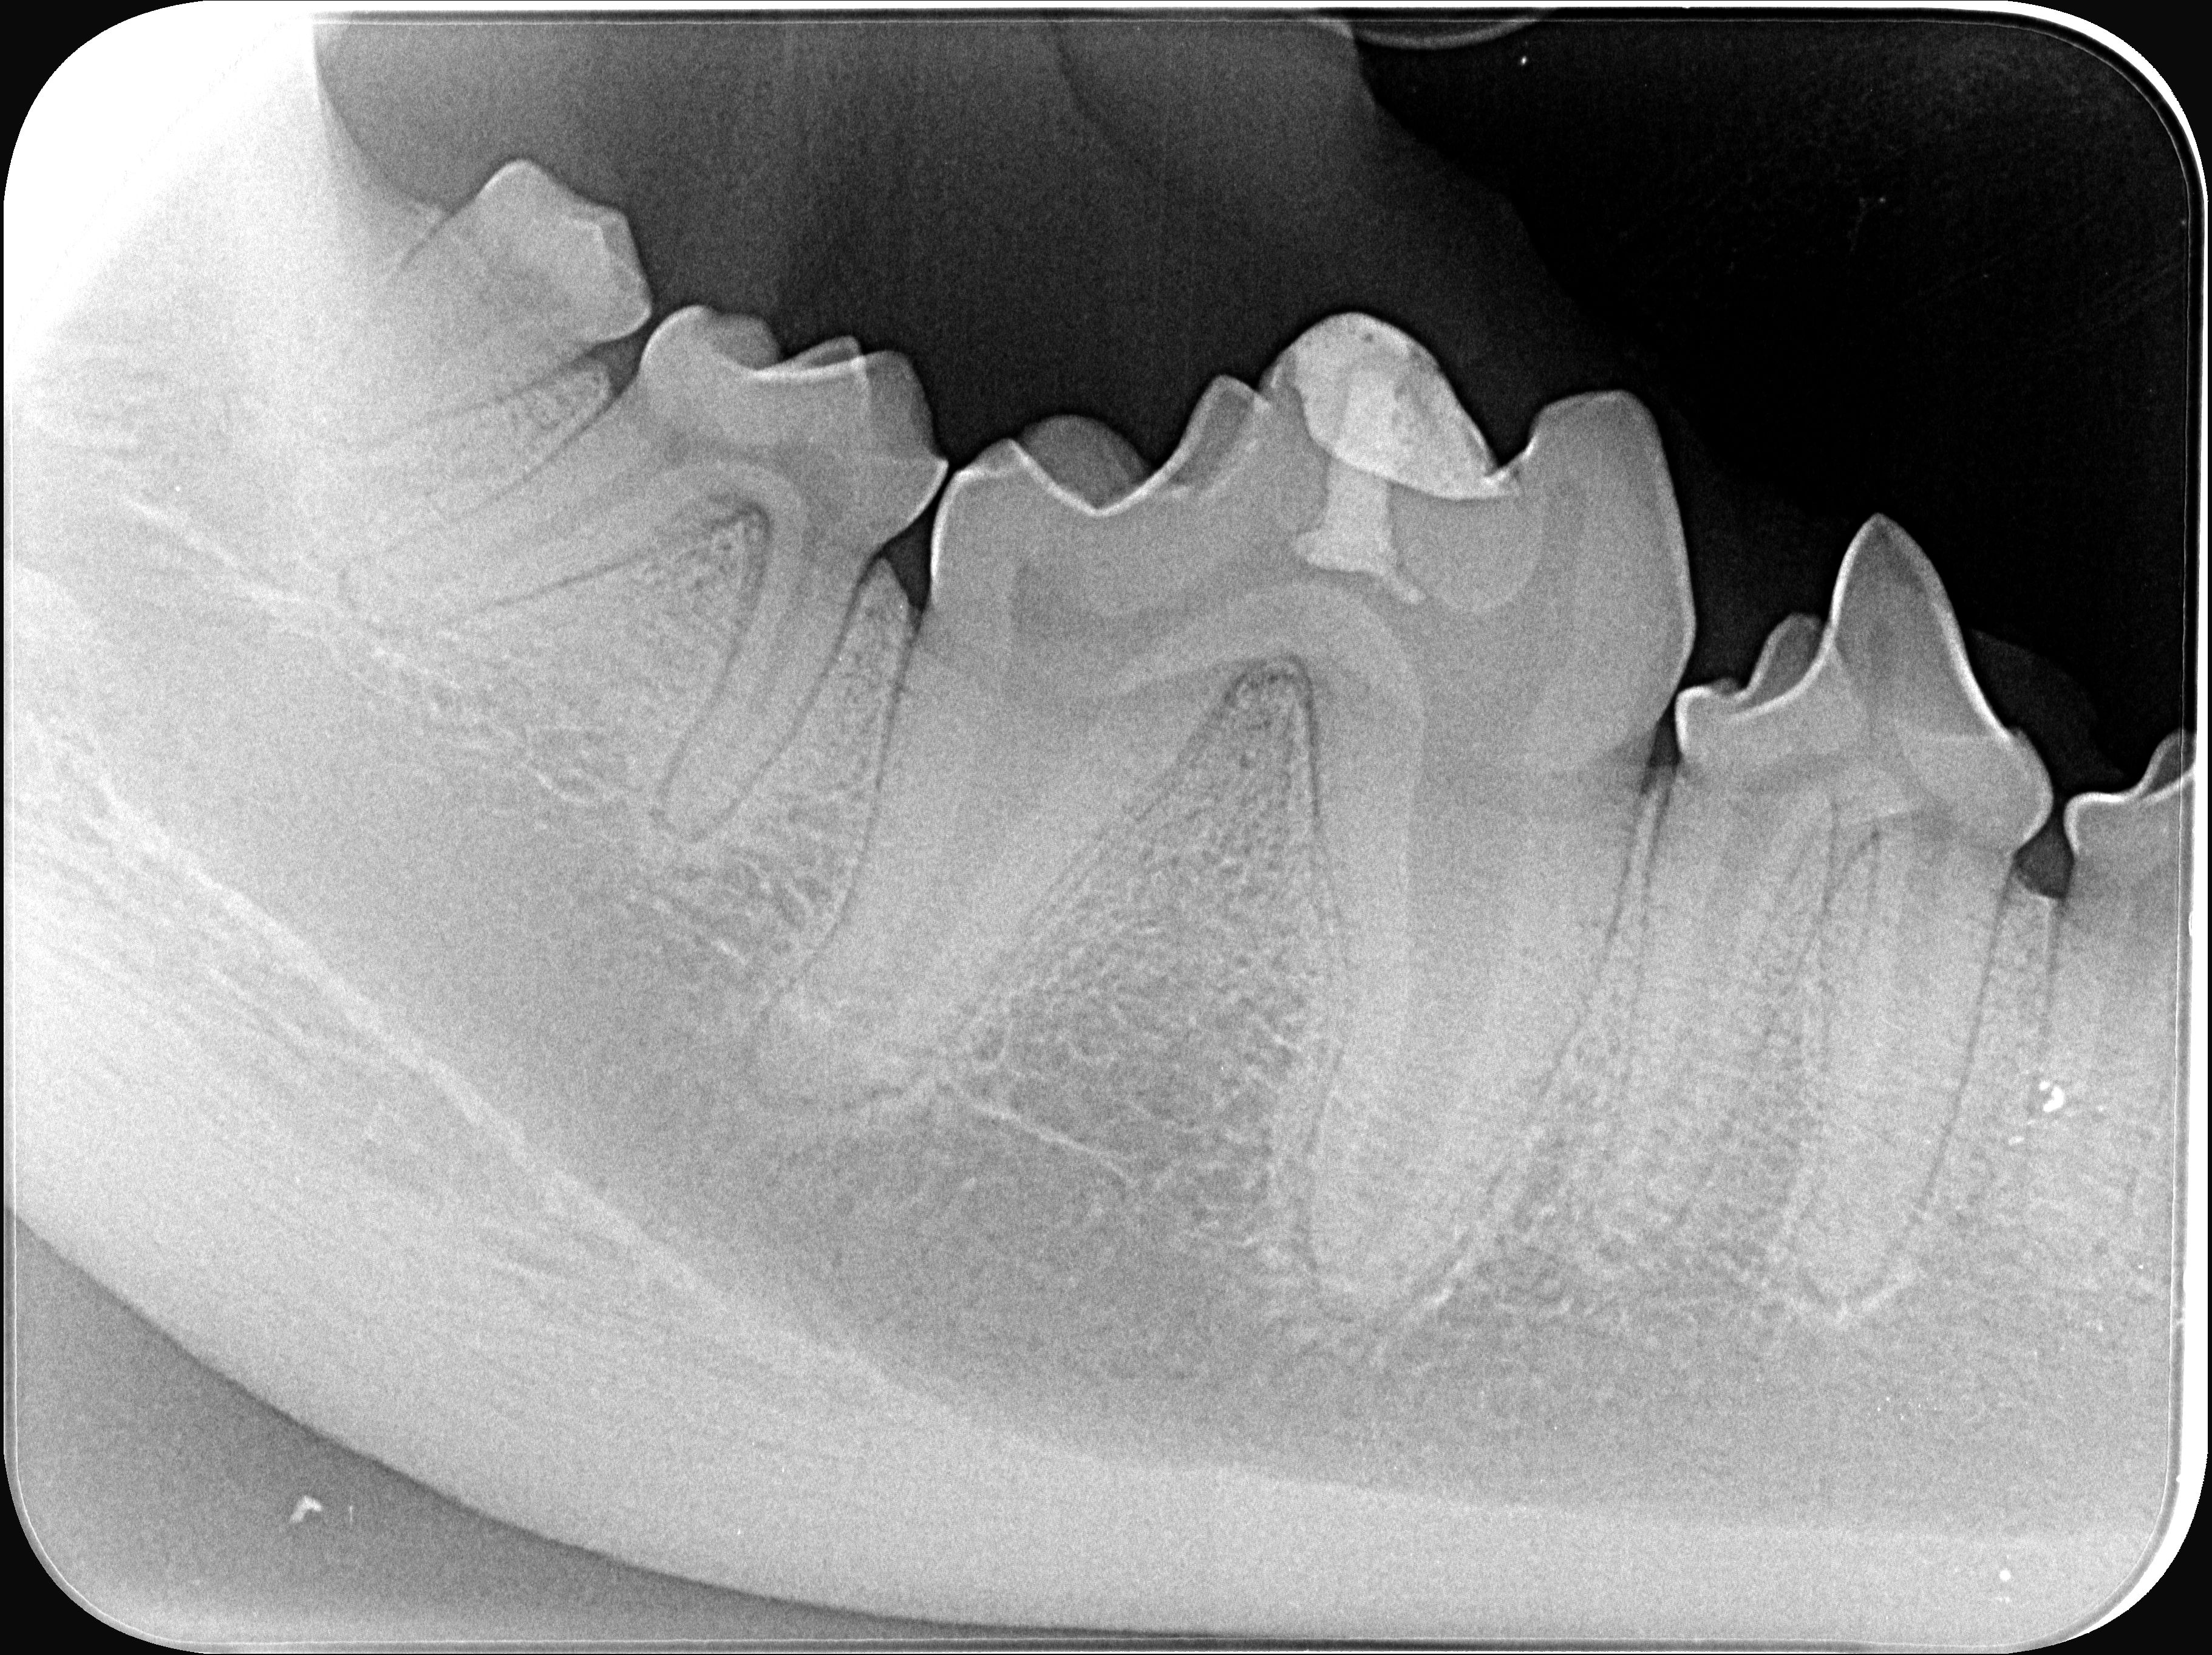

Gesunde Zähne sind für das Wohlbefinden Ihres Tieres essenziell, doch Zahnerkrankungen bleiben oft lange unentdeckt. Wir von Vets4Pets kümmern uns mit besonderer Sorgfalt um die Zahngesundheit Ihres Lieblings. Mithilfe unserer COHAT (Comprehensive Oral Health Assessment and Treatment) führen wir eine umfassende zahnmedizinische Untersuchung und Behandlung durch, die ein intraorales Zahnröntgen, eine detaillierte intraorale Befundung, eine professionelle Dentalhygiene sowie einen individuellen Behandlungsplan umfasst. Als spezialisierte Praxis bieten wir neben gängigen Behandlungen wie Extraktionen auch Leistungen, die nur Spezialisten vorbehalten sind. Dazu gehören zahnerhaltende Massnahmen wie Wurzelbehandlungen, Parodontalbehandlungen sowie Korrekturen von Zahn- und Kieferfehlstellungen. Unser Ziel ist es, Ihrem Tier Schmerzfreiheit und Lebensfreude zurückzugeben sowie versteckte Gesundheitsrisiken zu eliminieren. Vereinbaren Sie jetzt einen Termin für langfristige Zahngesundheit!

Wenn ein Tier krank ist, wünschen sich Halter:innen vor allem eines: schnell Klarheit darüber, was los ist. Genau dafür steht unsere moderne Inhouse-Diagnostik. In unserem eigenen Labor analysieren wir Blut- und Urinproben direkt vor Ort – schnell, zuverlässig und grösstenteils ohne die üblichen Wartezeiten auf Ergebnisse externer Labore. Mithilfe von digitalem Röntgen und intraoralem Zahnröntgen erkennen wir präzise und in hoher Bildqualität Probleme an Knochen, Gelenken, inneren Organen und Zähnen. So können wir akute Probleme nicht nur besser einschätzen, sondern auch chronische Erkrankungen frühzeitig erkennen und individuell behandeln. Für weiterführende ultrasonographische Untersuchungen arbeiten wir eng und vertrauensvoll mit Spezialisten für Bildgebung zusammen; auch für zyto- und histologische Untersuchungen besteht eine erfolgreiche Zusammenarbeit mit Experten unseres Vertrauens. Vertrauen Sie auf moderne Technik und langjährige Erfahrung – für eine sichere Diagnose!